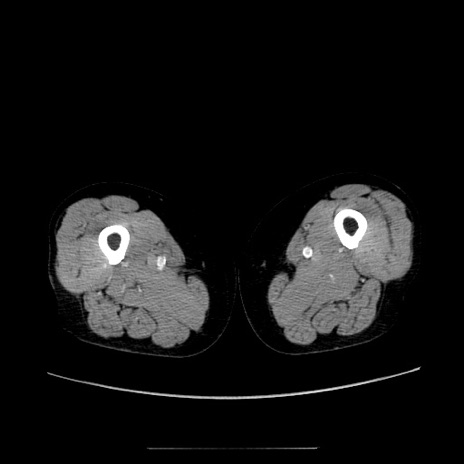

冠状断像

【症例】70歳代女性

【主訴】お腹が張る

【現病歴】1週間くらい前から腹部膨満の自覚あり。昨日夜から増悪したため、本日救急外来受診。

【身体所見】意識清明、BT 36.5℃、BP 165/106mmHg、HR 80bpm、SpO2 98%、腹部:膨満、軟、自発痛・圧痛なし、触診にて不快感あり、腸蠕動音:減弱

【データ】WBC 12600、CRP 1.04